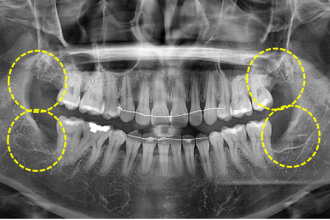

사랑니발치

굿프렌즈 치과 임상 케이스